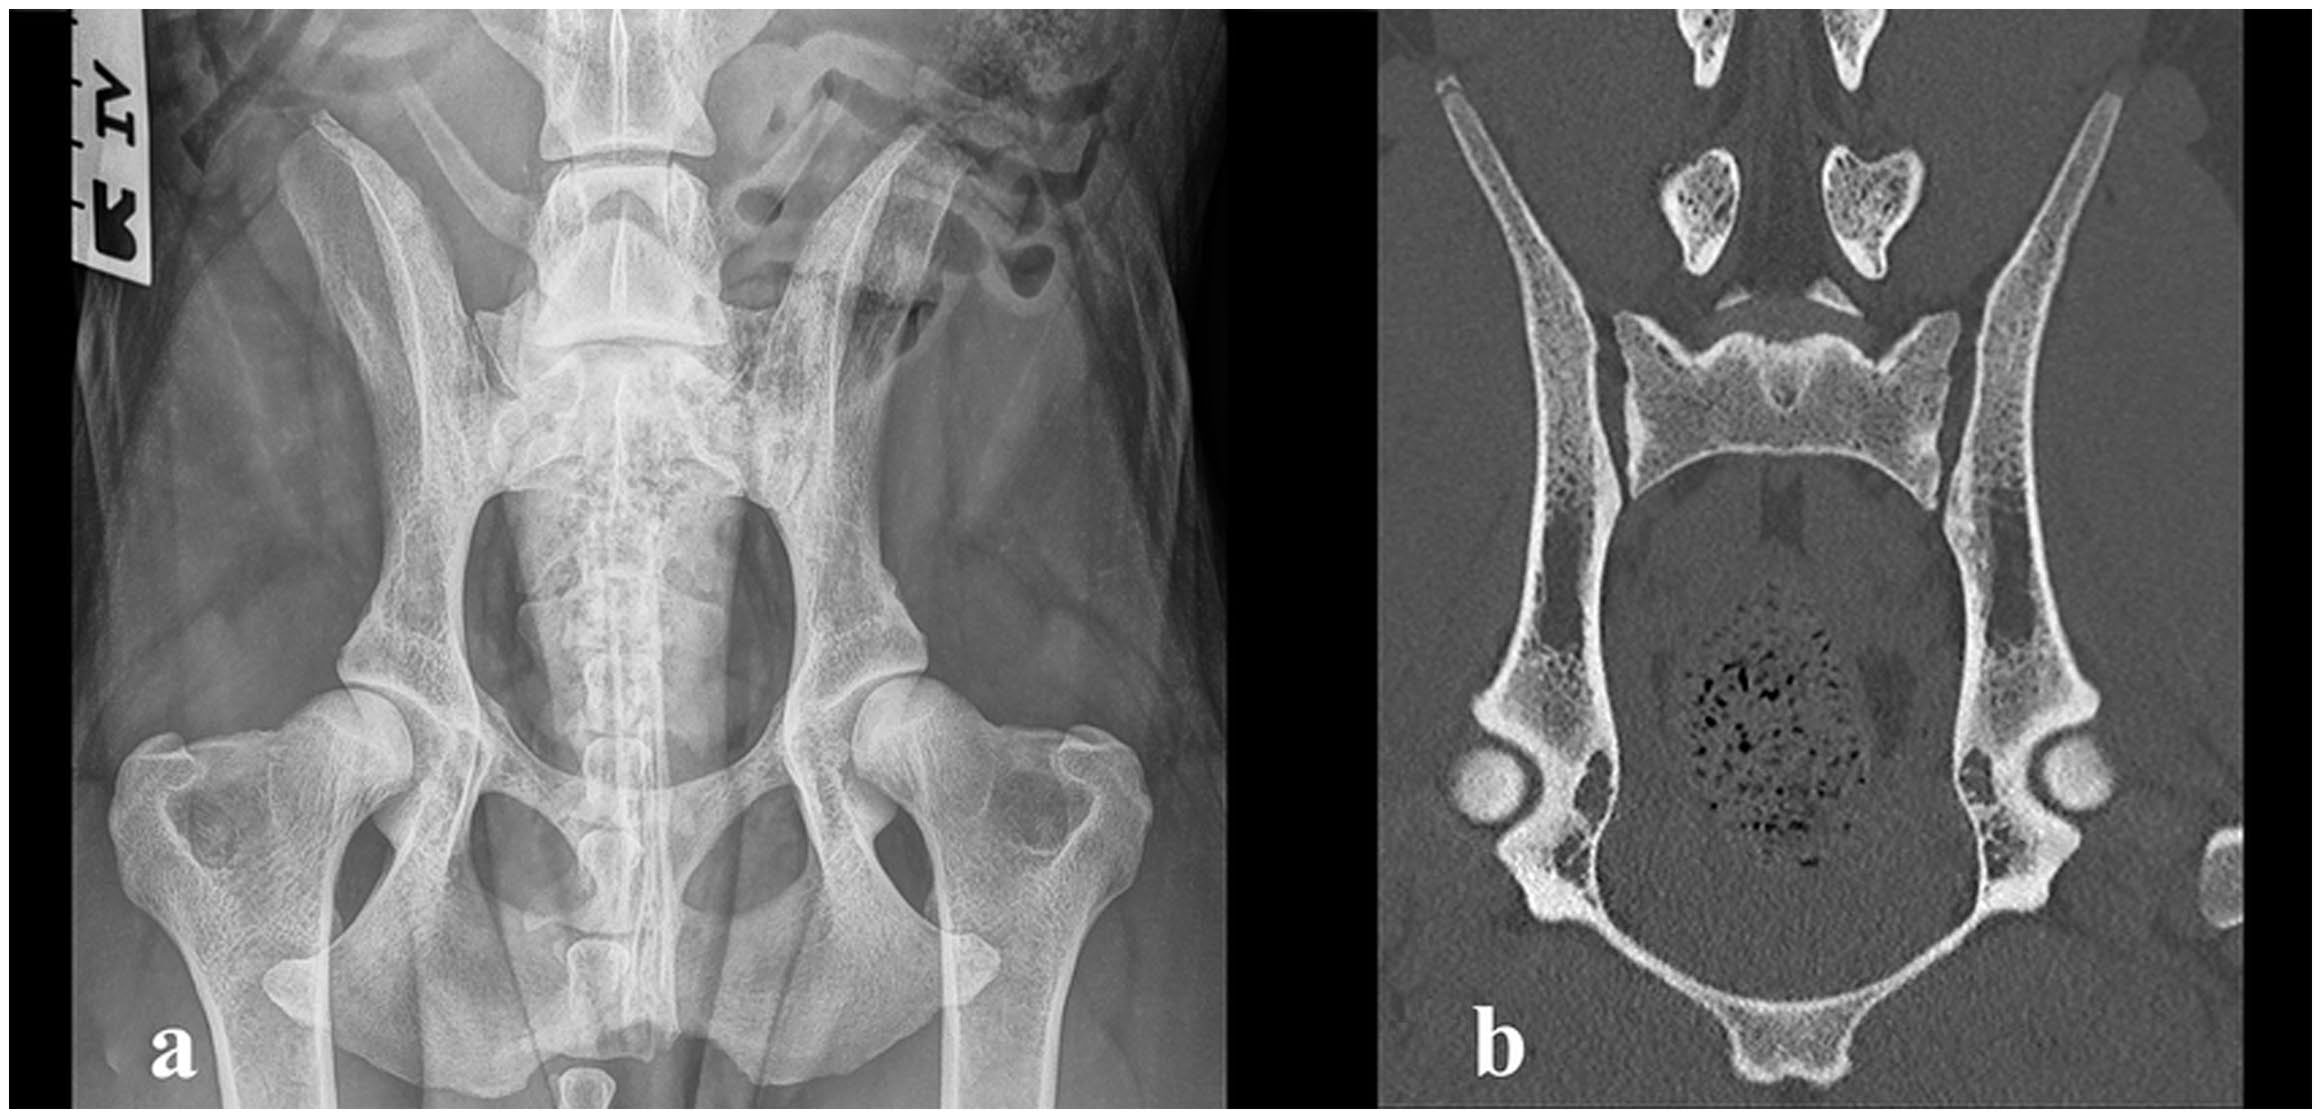

1.5年后,主人报告称该犬保持正常的活动能力,没有临床不适。触摸骶髂关节和腰骶部时无疼痛表现。髋关节的活动范围正常且无疼痛。临床上观察到轻度跗骨外旋。X光和CT未显示侵蚀性或硬化性病变的迹象,骶髂关节的外观被认为是正常的(下图)。在国际犬联官方的髋关节发育不良筛查中,髋关节被评定为D/D(中度髋关节发育不良)。

↑ (a)1.5年后拍摄的腹背位X光片,显示骶髂关节的侵蚀性病变完全消失,并显示出中度髋关节发育不良。(b)CT图像(冠状面)显示病变完全消失。